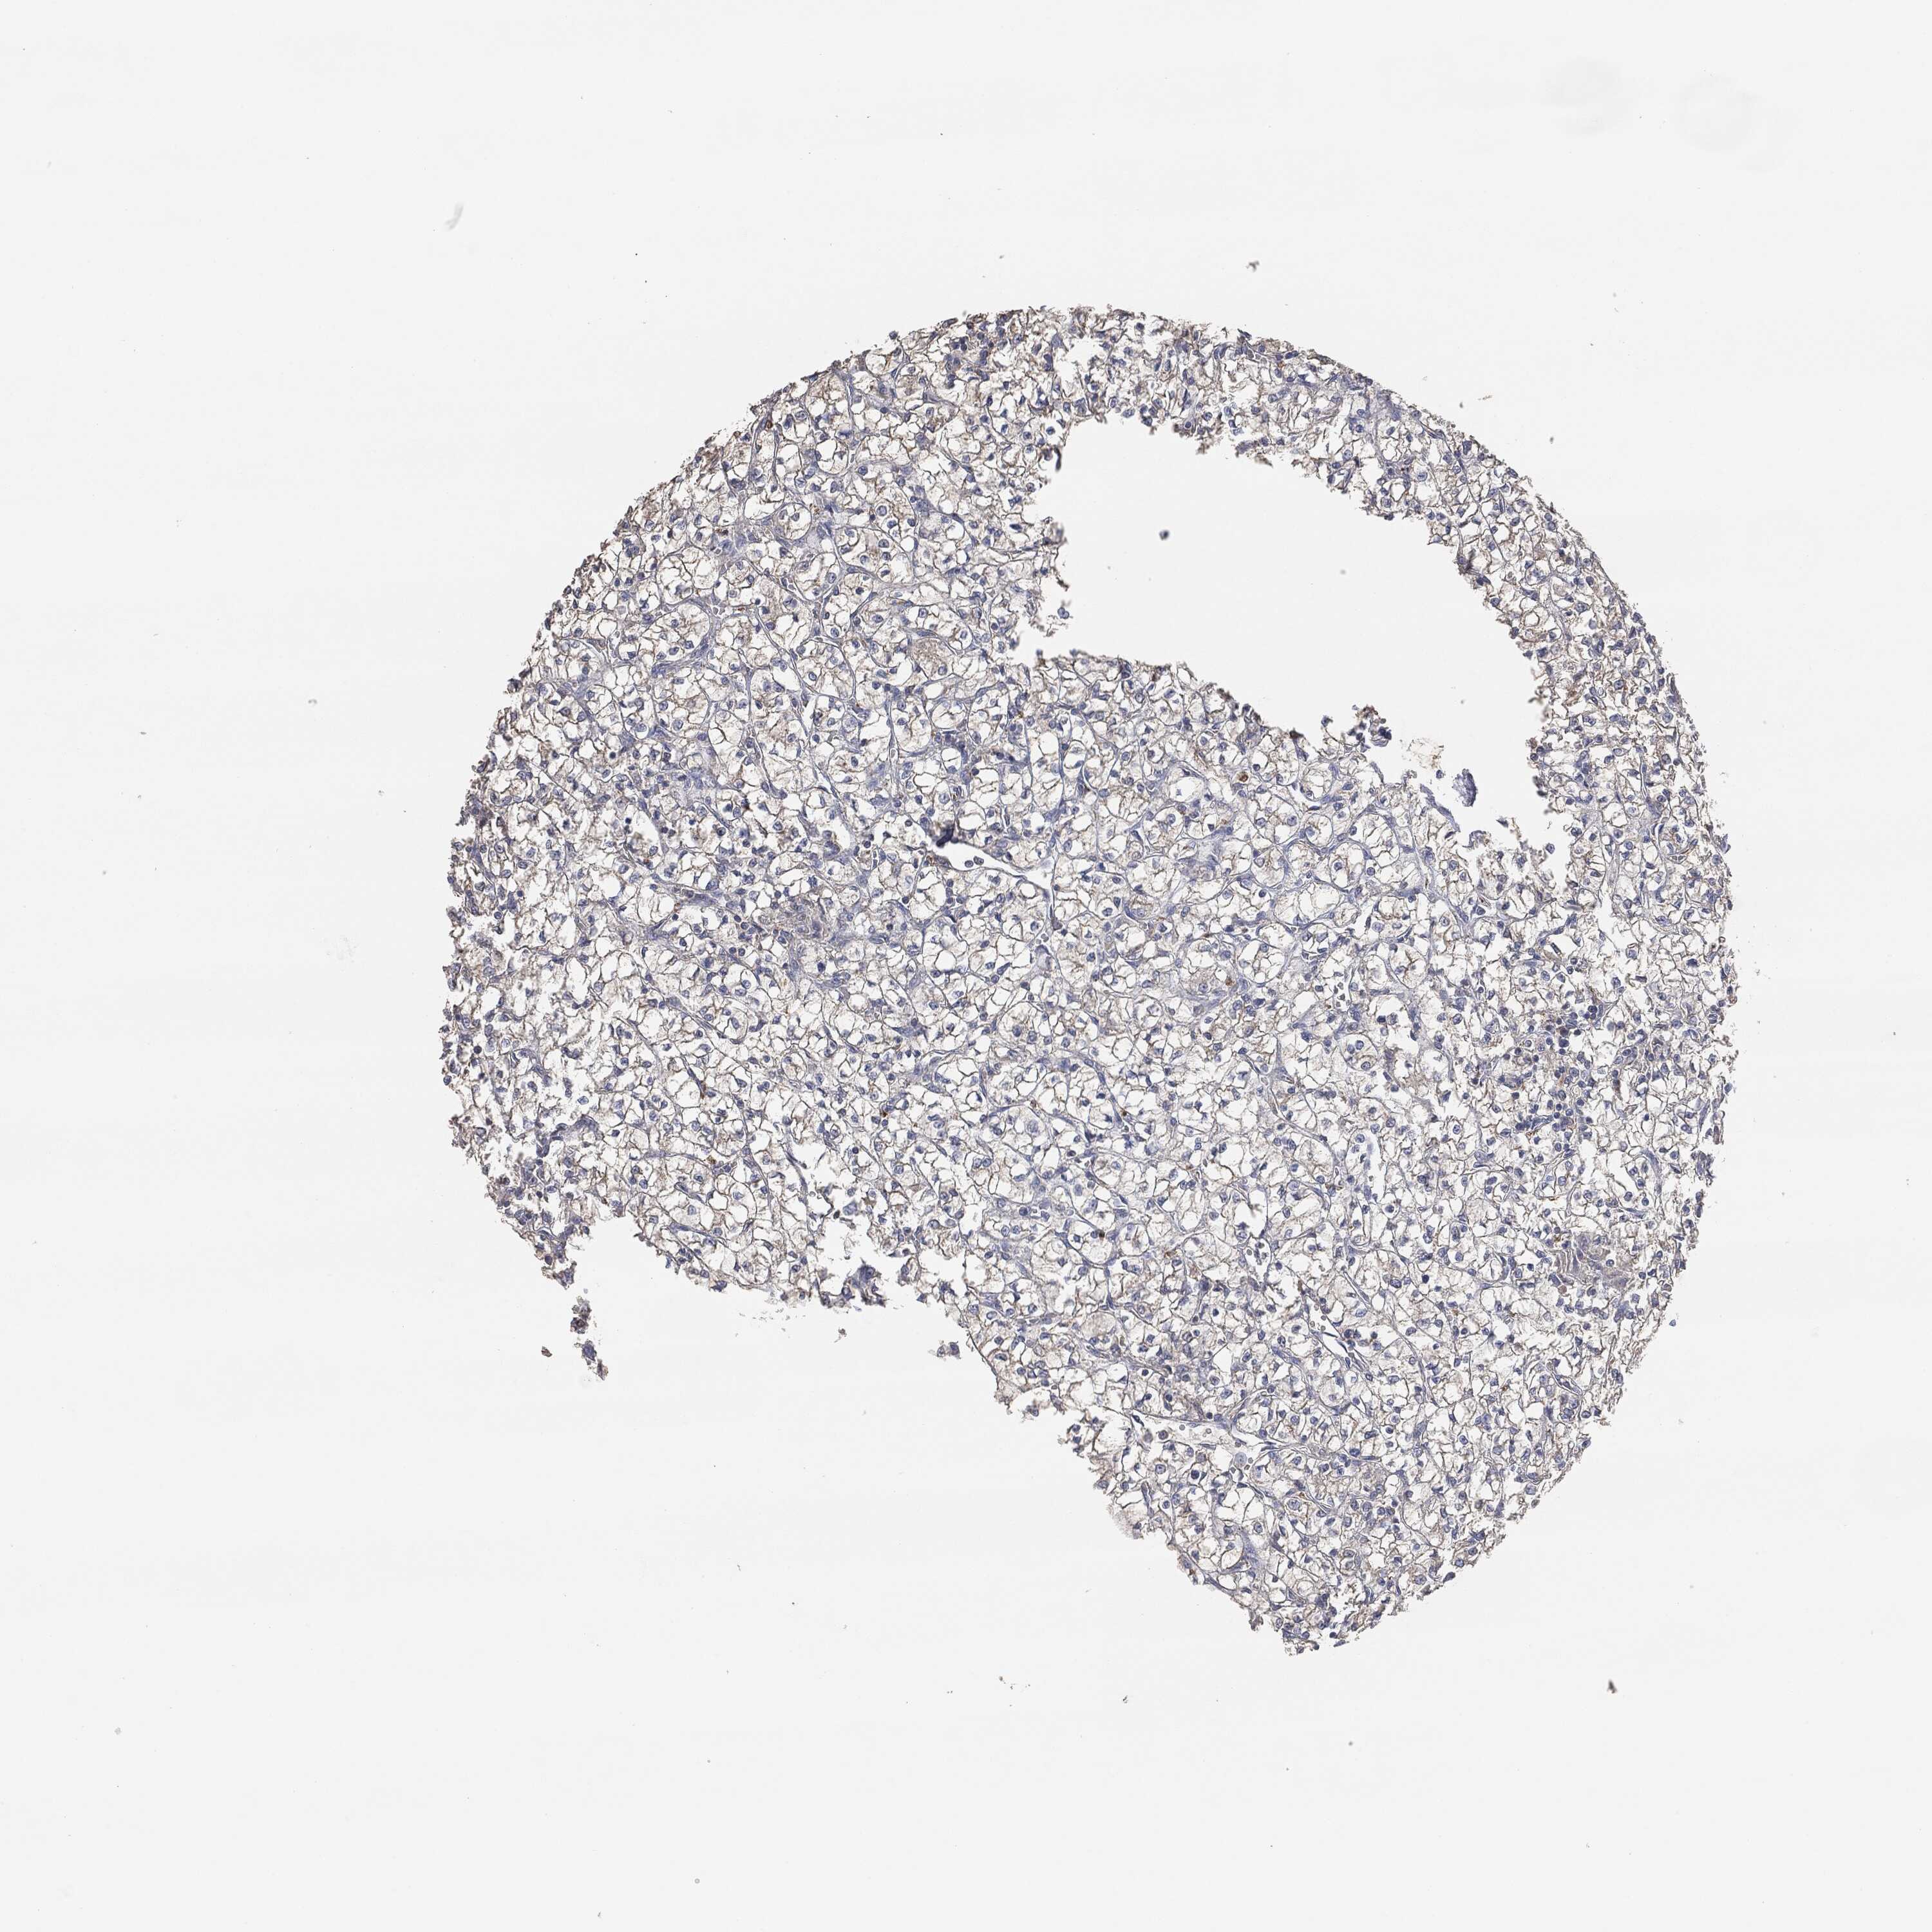

CANCER RENAL CANCER Show tissue menu

KICH TCGA KIRC TCGA KIRC VALIDATION KIRP TCGA PROTEIN RCC CPTAC PROTEIN EXPRESSION